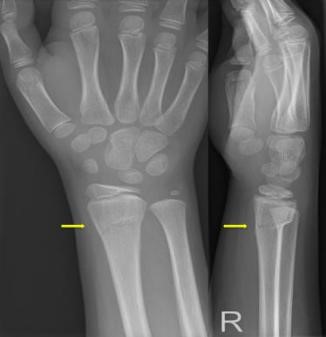

Uw kind heeft een kleine breuk in de ellepijp of het spaakbeen ter hoogte van de pols (greenstick fractuur). Het is een knikje in het bot. We behandelen dit met een brace en een sling. Dit is een soort mitella.

Deze greenstick fractuur van de pols of onderarm komt vaak voor bij kinderen. Het wordt ook wel een twijgbreukje genoemd, omdat het knikje in het bot lijkt op het buigen van een flexibel takje van een boom. We behandelen deze breuk met een afneembare brace en een sling. Dit is een soort mitella.